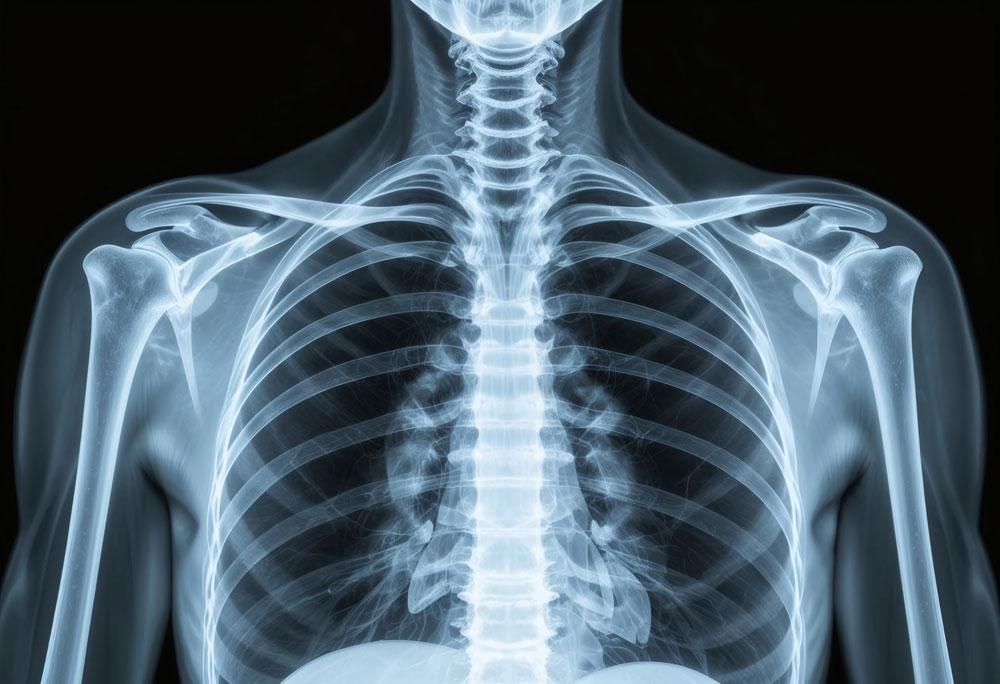

13 new DEXA scanners are to be rolled out across the country, set to deliver and extra 29,000 bone scans each year.

The scanners are equipped with advanced technology to identify with minute detail the quality of a patient’s bones, with more than one in three women and one in five men experiencing a fracture due to osteoporosis in their lifetime.

Sue Mann, clinical lead for women’s health at NHS England, said: "This is a welcome targeted investment for the NHS Trusts across England set to receive these new scanners from this month - they measure tiny reductions in bone density that can help us diagnose osteoporosis in its early stages, before you break a bone.